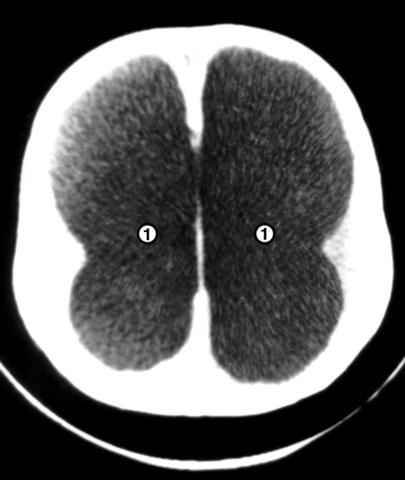

Рис. 4. Компьютерные томограммы головы грудного ребенка с гидроцефалией: на срезах, выполненных на разных уровнях, видно резкое расширение боковых (1) и третьего (2) желудочков.